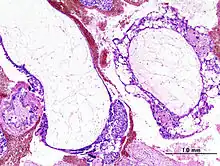

Histopathologic image of hydatidiform mole (complete type). H&E stain.

A hydatidiform mole is a pregnancy/conceptus in which the placenta contains grapelike vesicles (small sacs) that are usually visible to the naked eye. The vesicles arise by distention of the chorionic villi by fluid. When inspected under the microscope, hyperplasia of the trophoblastic tissue is noted. If left untreated, a hydatidiform mole will almost always end as a spontaneous abortion (miscarriage).

Based on morphology, hydatidiform moles can be divided into two types: in complete moles, all the chorionic villi are vesicular, and no sign of embryonic or fetal development is present. In partial moles, some villi are vesicular, whereas others appear more normal, and embryonic/fetal development may be seen but the fetus is always malformed and is never viable.